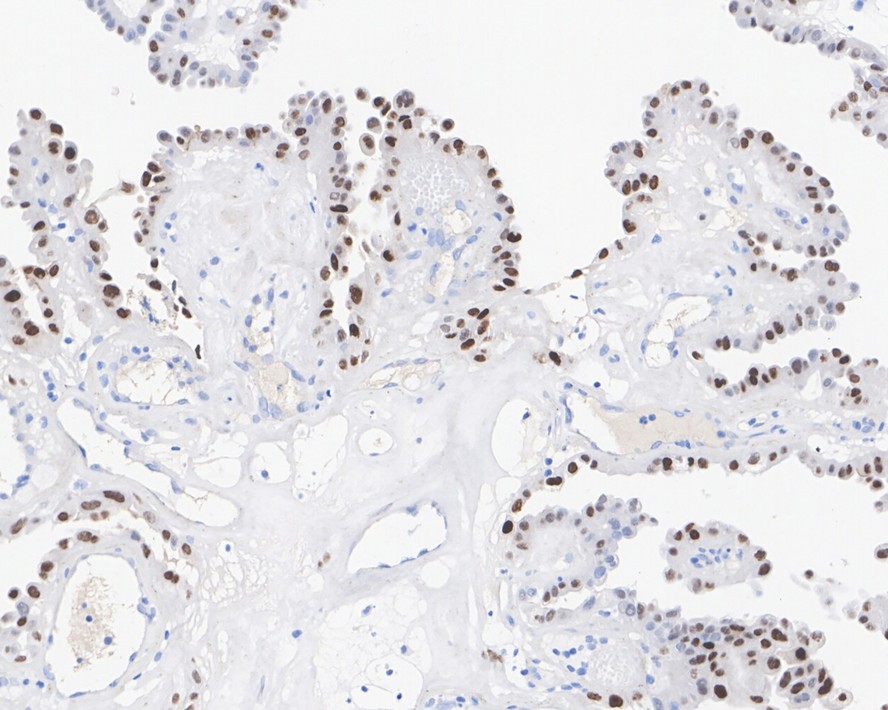

Catalog# HA601017

p21 Mouse Monoclonal Antibody [A8C12]

IHC-P

Human